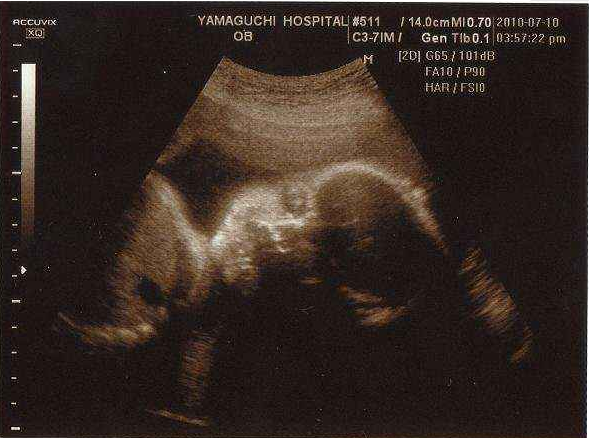

即便成功怀孕,宋女士也不敢有任何松懈,生怕再次流产,孕42天,宋女士孕检胎心正常,宝宝发育良好,目前宋女士已经在家待产。